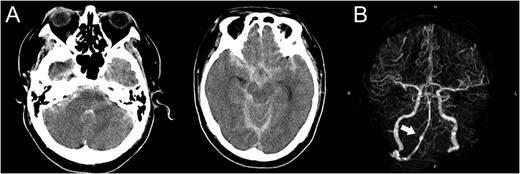

A 48-year-old man was admitted to our hospital because of loss of consciousness after a sudden nuchal pain. Brain computed tomography (CT) showed diffuse SAH (Fig. 1A). The following CT angiogram showed a fusiform aneurysm at the right vertebral artery with contralateral hypoplasia (Fig. 1B). The endovascular procedure was performed under general anesthesia. The patient received a loading dose of 200 mg of aspirin and 300 mg of clopidogrel via a nasogastric tube. A preoperative angiogram showed VAD with a blister at the pseudolumen (Fig. 2A). Initially, a stent (Enterprise, 4.5 mm × 37 mm; Codman, Raynham, MA, USA) was deployed from the basilar artery to the right vertebral artery. A second stent (Enterprise2, 4.0 mm × 30 mm) then overlapped the first stent, covering the pseudolumen (Fig. 2B). Coiling was performed from a microcatheter (Excelsior SL-10/45; Boston Scientific, Fremont, CA, USA), which was jailed in the pseudolumen. After the first coil perforated the blister, a balloon catheter (Scepter C, 4.0 mm × 15 mm; Microvention, Tustin, CA, USA), which was exchanged with a stent delivery catheter, was inflated in the stent. All five small platinum coils (Target nano, 2 mm × 4 cm and 1.5 mm × 2 cm; Stryker, Fremont, CA, USA) completely occluded the pseudolumen (Fig. 2C), and the right vertebral artery was preserved (Fig. 2D). Magnetic resonance imaging, which was obtained 3 weeks after the procedure, showed right cerebellar infarction without damage of the brainstem (Fig. 3). The patient recovered and returned to his former job after 2 weeks of intensive care and 3 months of rehabilitation therapy. An angiogram, which was obtained 6 months after procedure, showed no recurrence of VAD (Fig. 4).

(A) Computed tomography images show diffuse subarachnoid hemorrhage. (B) Computed tomography angiogram shows a fusiform aneurysm at the right vertebral artery (arrow) with contralateral hypoplasia.